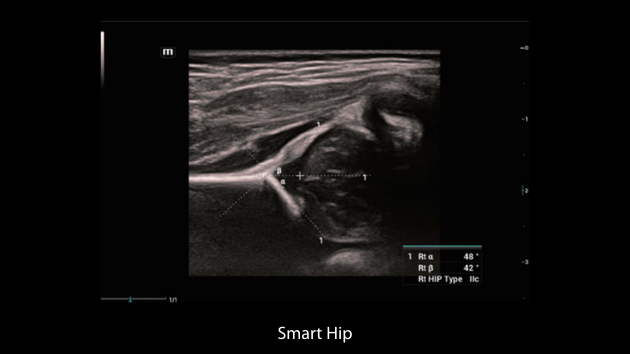

Nuewa I9, kad?nlara ve yenido?anlara y?nelik sa?l?k hizmetleri i?in ?zel olarak tasarlam??t?r ve i?ten d??a yenilik?i bir deneyim sunmaktad?r. Bu yenilikler, karma??k klinik senaryolara ili?kin derinlemesine bilgilere dayal? olarak geli?tirilmi?tir ayr?ca do?ru ve zaman?nda yan?tlar?n yan? s?ra, ola?an├╝st├╝ verimlilik ve ola?an├╝st├╝ kullan?c? deneyimi sunar.